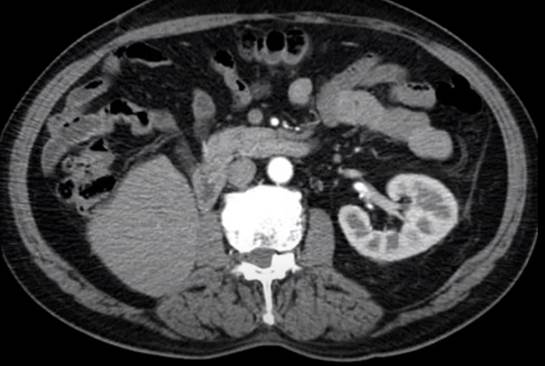

Ausencia de unidad renal derecha y unidad renal izquierda con cambios postquirúrgicos tras la nefrectomía parcial laparoscópica.

Imagen 4 Urotomografía de control